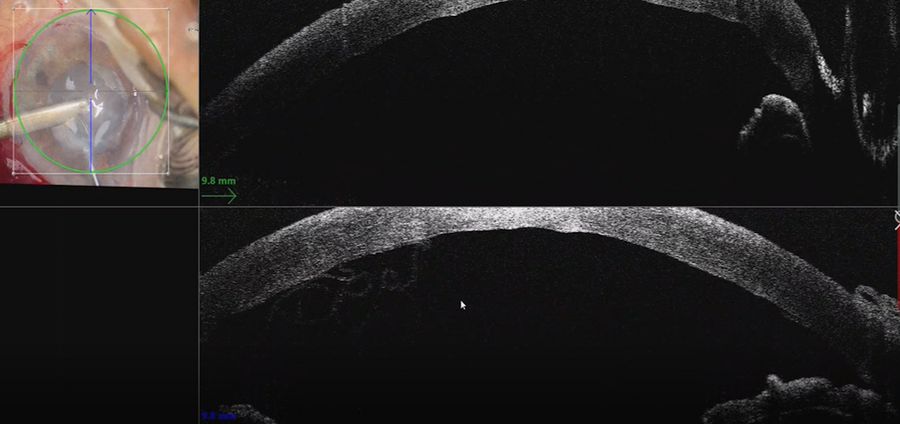

In this case, a Descemet rhexis was created. The clear red reflex on the Proveo 8 with EnFocus intraoperative OCT allowed clear visualization of Descemet’s membrane peeling and endothelium.

When performing the strip, the intraoperative OCT provided live confirmation of where DM was present. This is particularly helpful when there is a poor view e.g. in this case of ocular trauma. The OCT showed the separation of Descemet’s membrane very clearly.